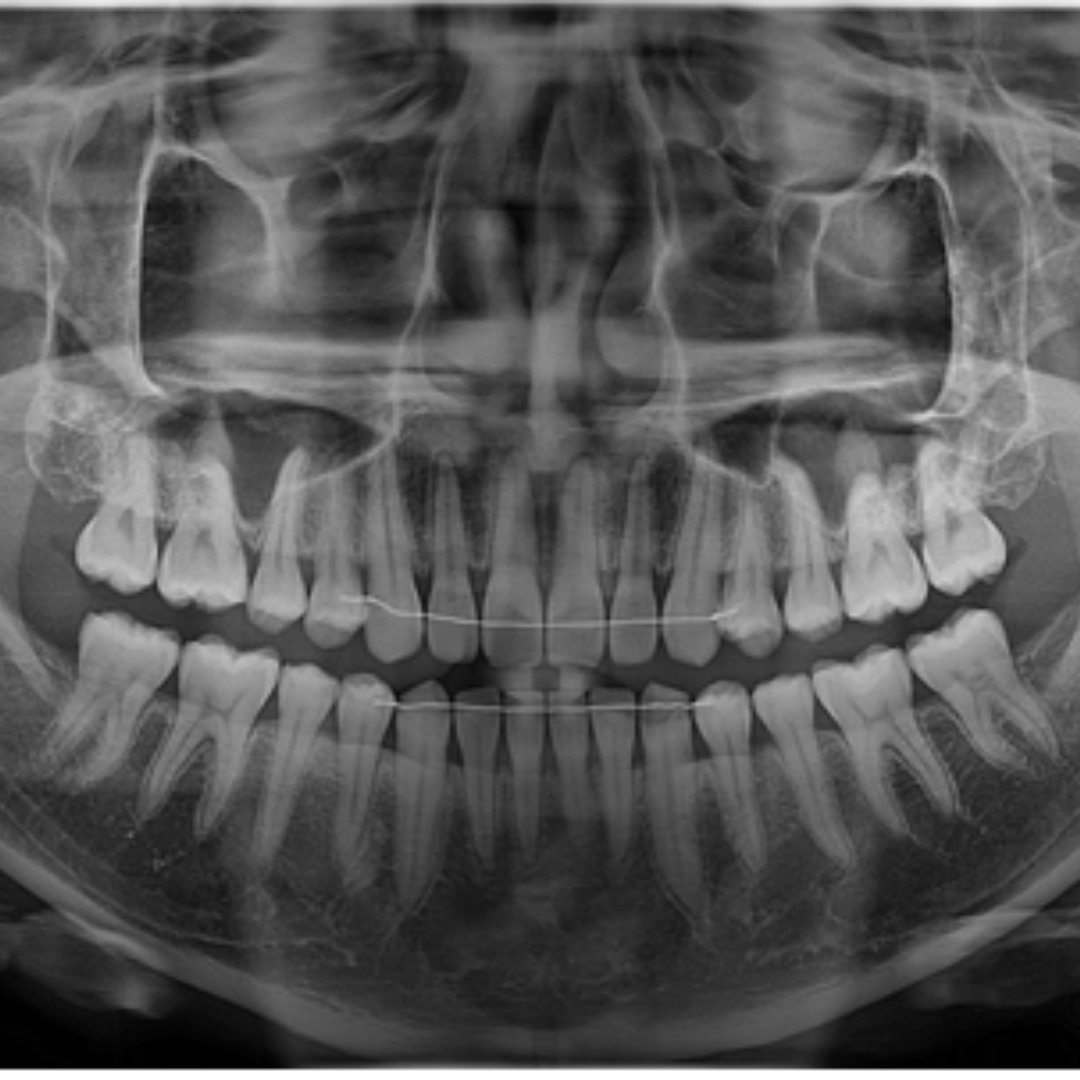

돌출입, 덧니의 발치 교정 치료 증례

돌출입과 덧니를 고민으로 내원하신, 10대 청소년 환자 분의 증례를 소개드리겠습니다.촬영일시 : ..